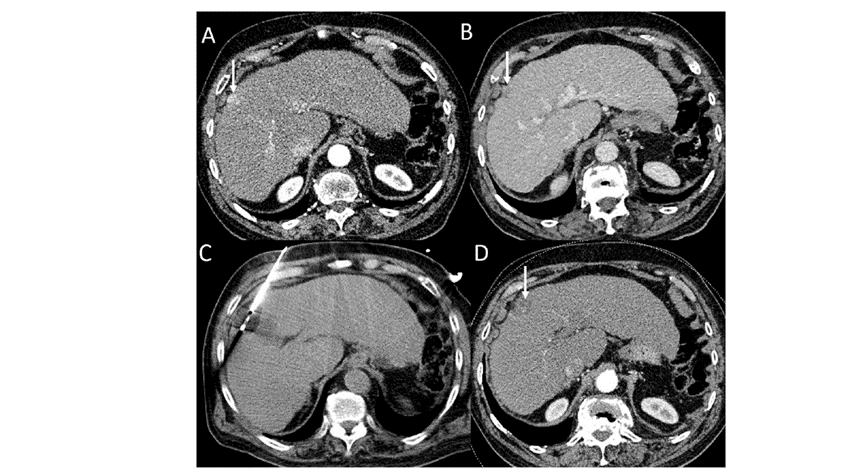

CT引導下冷凍消融

undefined

79 歲男性,肝轉移(結直腸癌)腫瘤的完全消融病例

( a ) 軸向 MRI 和 ( b ) 軸向 CT 顯示肝S8段有一個16mm的病灶,鄰近肝緣。

( c )冷凍消融期間CT顯示放置了2個冷凍探針,低密度冰球包圍病灶。

(d)術后1個月隨訪 CT顯示冰球對應的壞死區(qū)域,未見復發(fā)。

(e)術后6個月的CT,壞死區(qū)域縮小,未見復發(fā)。

(f)與基線影像(g)相比,12個月后的FDG-PET/CT顯示未見FDG攝取。

62歲女性,肝轉移(卵巢癌)腫瘤的完全消融病例

(a)軸向CT顯示病變位置毗鄰心臟和上腔靜脈(黑色箭頭)。

(b)術中軸向CT掃描:使用三個冷凍探針。

(c)冠狀面和(d)矢狀面顯示冰球毗鄰心包。

1個月后的軸向(e)和冠狀位(f)增強CT掃描顯示低密度區(qū)域,由于肉芽組織反應引起的邊緣增強。